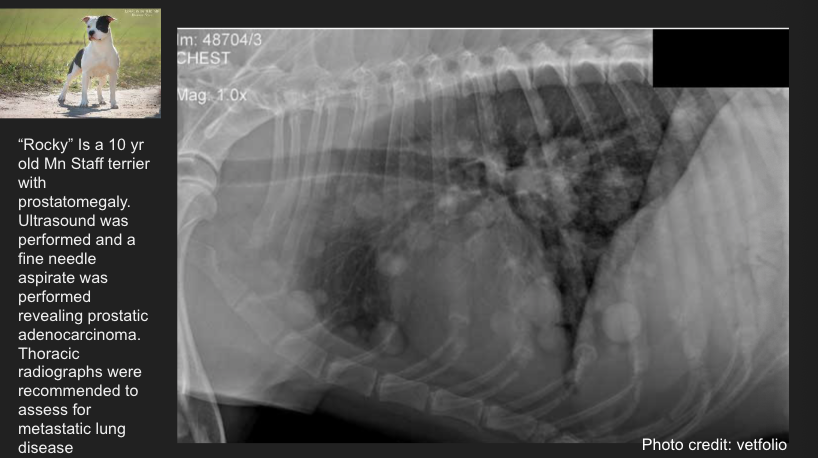

Lung pattern?

Structured interstitial pattern (metastatic disease)